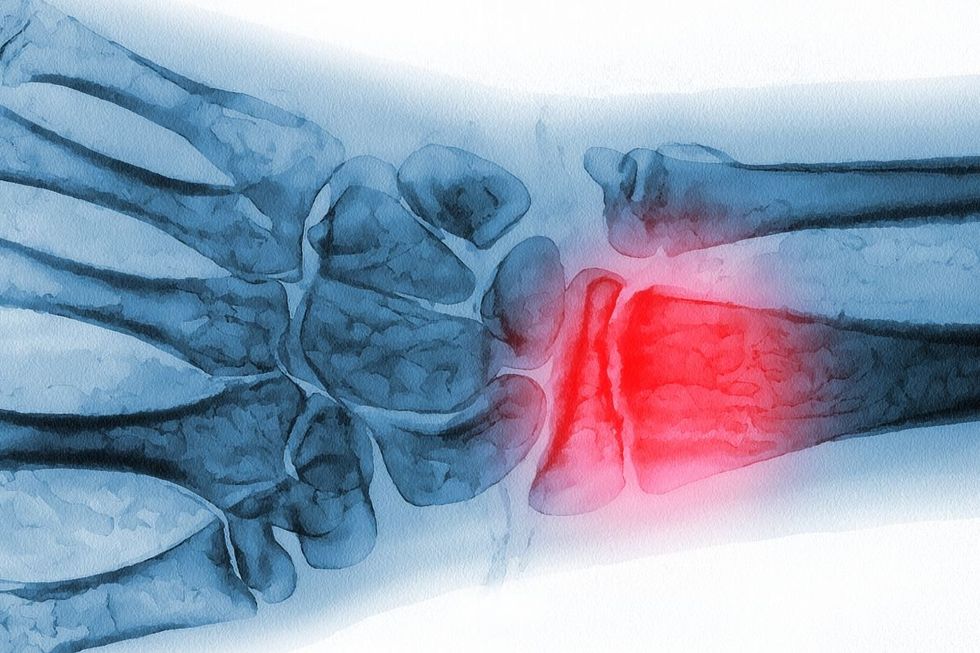

Everyday habits might be putting our bones at risk

|

GETTY